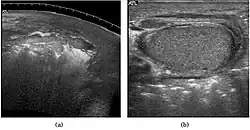

Teratoma Although teratoma is the second most common testicular tumor in children, it affects all age groups. Mature teratoma in children is often benign, but teratoma in adults, regardless of age, should be considered malignant. Teratomas are composed of all three germ cell layers, i.e. endoderm, mesoderm and ectoderm. At ultrasound, teratomas generally form well-circumscribed complex masses. Echogenic foci representing calcification, cartilage, immature bone and fibrosis are commonly seen [Fig. 5]. Cysts are also a common feature and depending on the contents of the cysts i.e. serous, mucoid or keratinous fluid, it may present as anechoic or complex structure [Fig. 6].

Fig. 5. Teratoma. A plaque-like calcification with acoustic shadow is seen in the testis. -

Fig. 6. Mature cystic teratoma. (a) Composite Image. Mature cystic teratoma in a 29-year-old man. Longitudinal sonography image of the right testis shows a multilocular cystic mass. (b) Mature cystic teratoma in a 6-year-old boy. Longitudinal sonography of the right testis shows a cystic mass containing calcification with no obvious acoustic shadow.